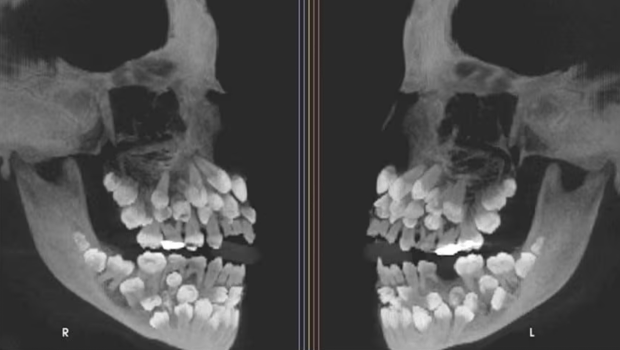

巴西一名11岁女童被发现口内有81颗牙,包括18颗乳牙、32颗恒牙及31颗多生牙(supernumerary teeth),远超成人正常32颗恒牙的数量。此病例于《美国正畸与牙面骨科杂志》中发表,引起全球学界关注。

▲巴西一名11岁女童被发现口内有81颗牙,包括18颗乳牙、32颗恒牙及31颗多生牙(supernumerary teeth)。《美国正畸与牙面骨科杂志》

这名11岁女童因需拔除一颗上颌乳牙而前往朱伊斯迪福拉联邦大学牙科医院就诊,当时临床检查并未发现明显异常,但X光检查结果令人瞠目结舌,因揭示其口内共有81颗牙,其后证实女童患有多牙症。研究团队进一步使用锥形束计算机断层扫描(CBCT)确认牙齿的精确位置及形态,发现多生牙分布于牙弓各处,部分深埋于牙龈内,形态异常,难以与正常牙齿区分。